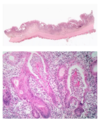

What is this?

wet cornflakes appearance - peusomembranous colitis

What is this image showing?

volcanic eruption -> pseudomembranous colitis